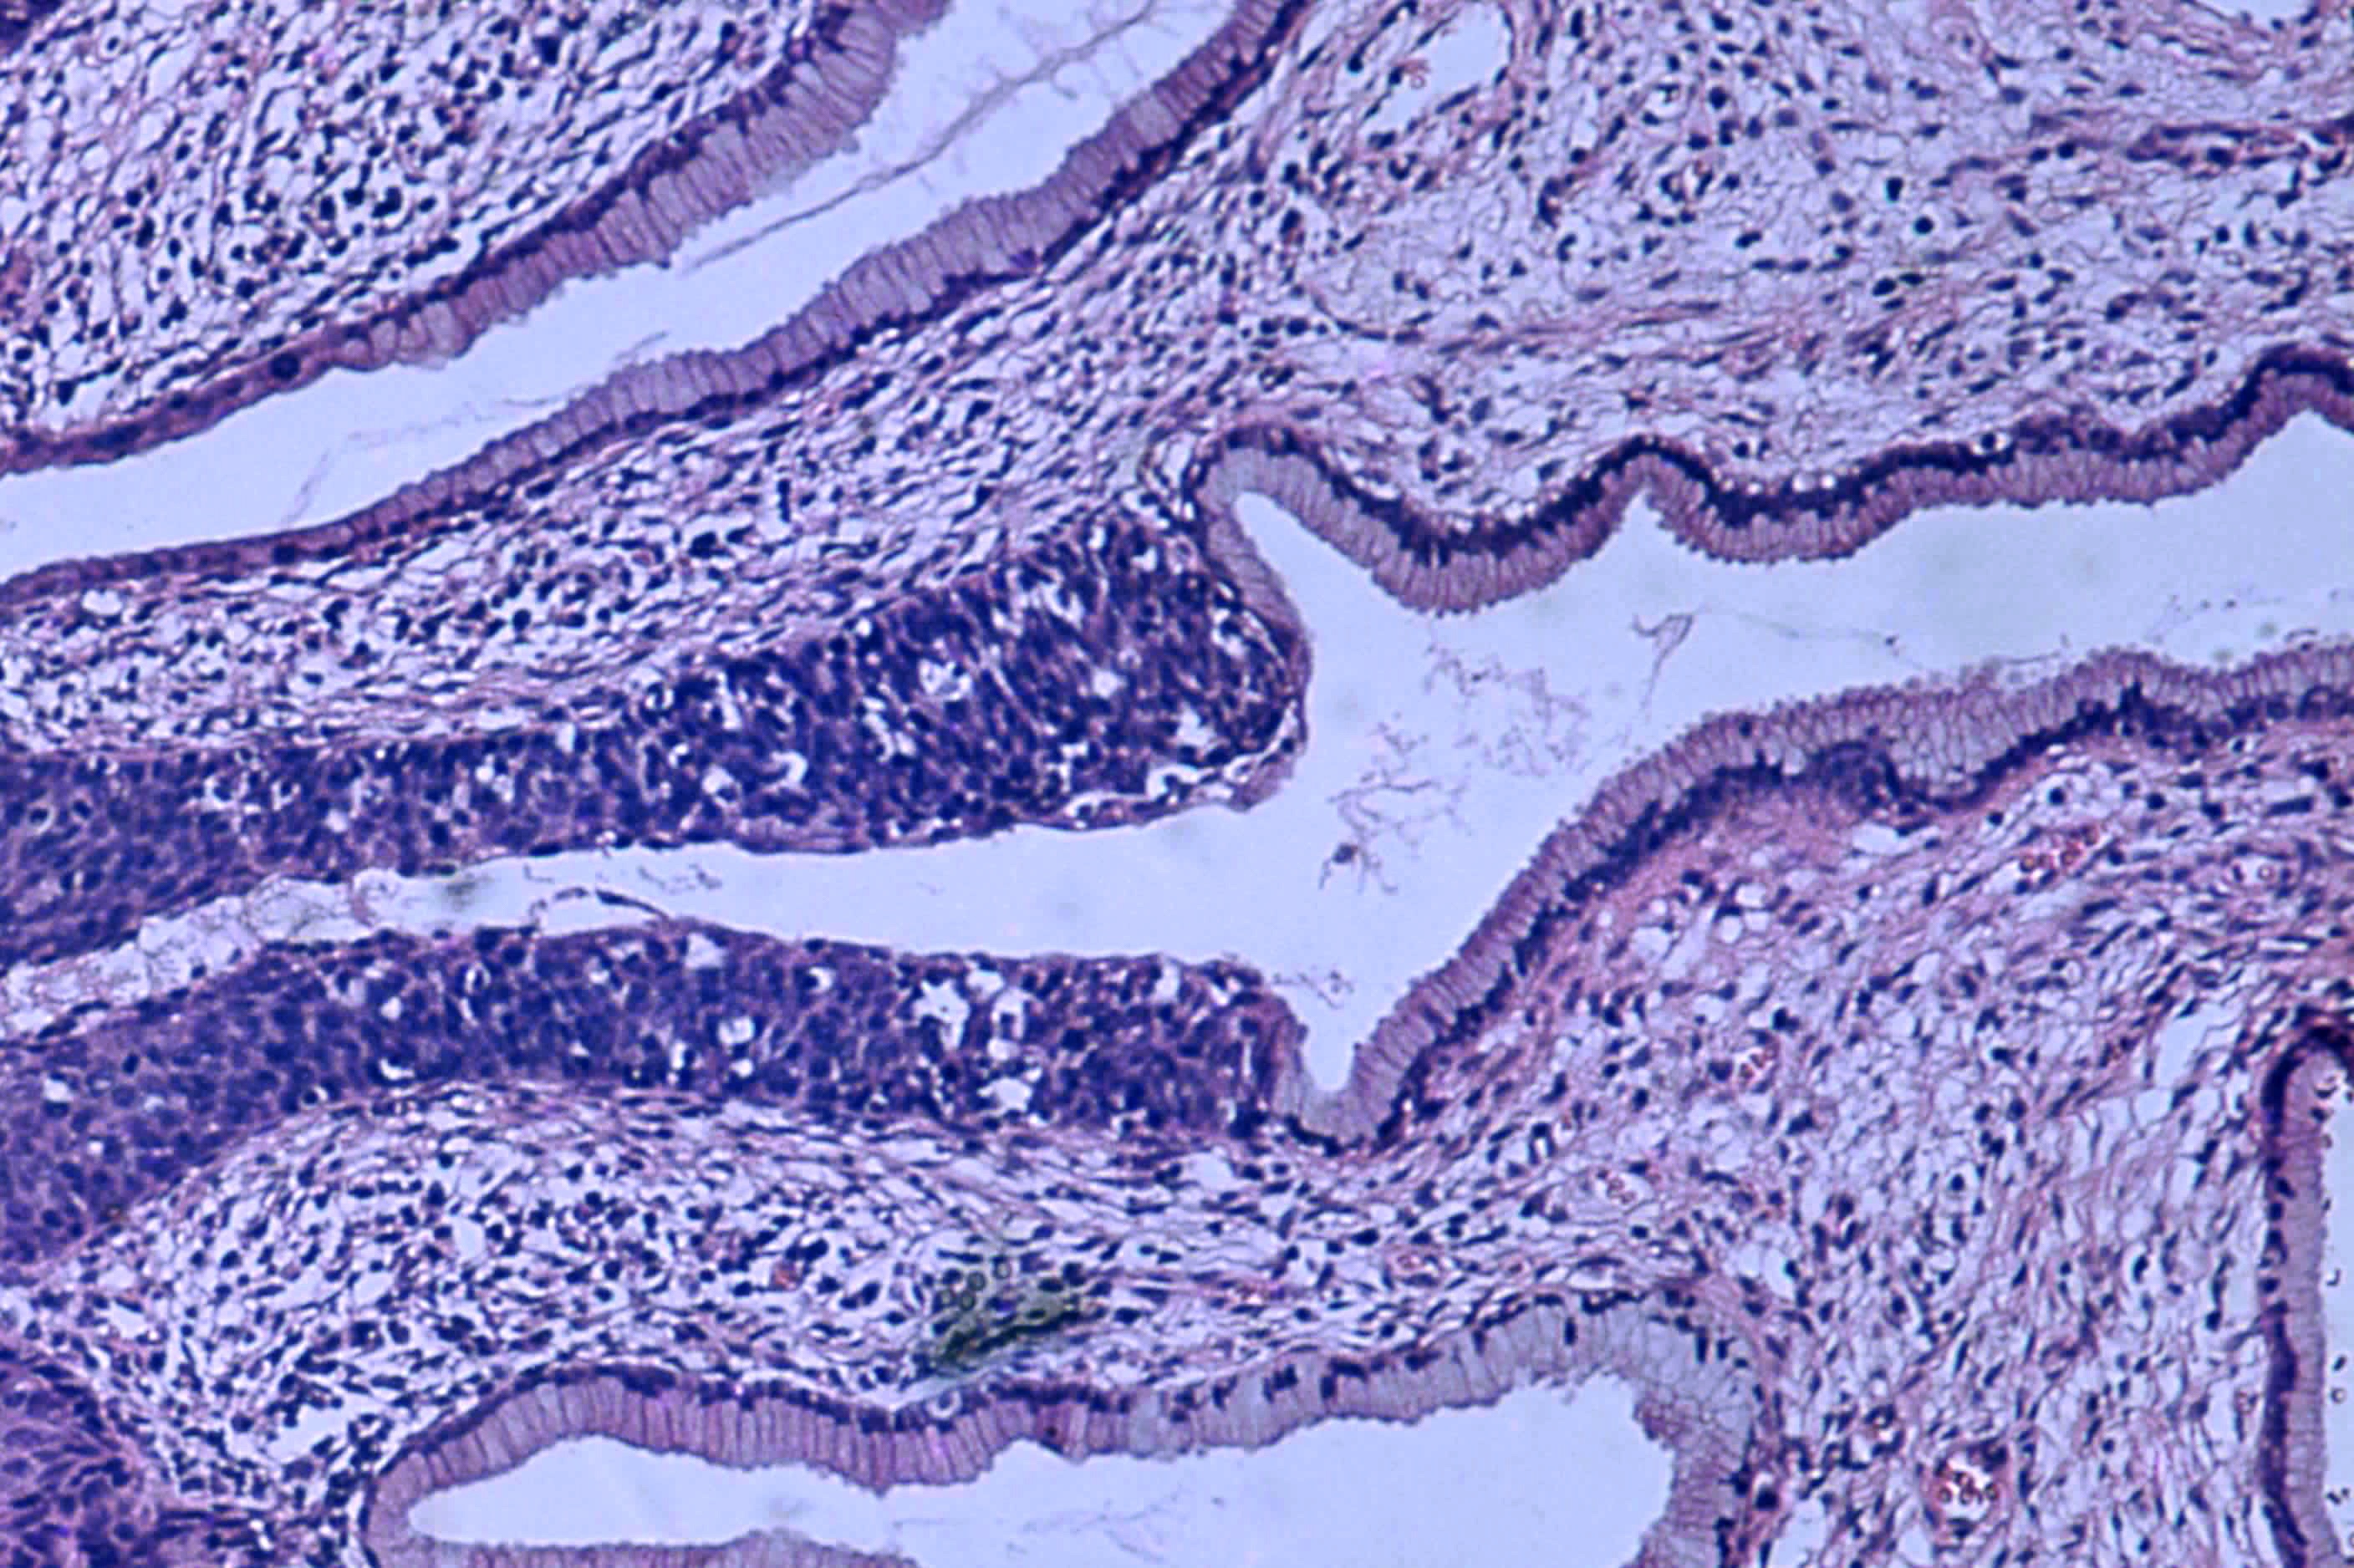

(Image Description:  Cytology  showing  cervical  cancer – specifically squamous cell carcinoma – in the cervix.  (Image Credit: National Cancer Institute) )